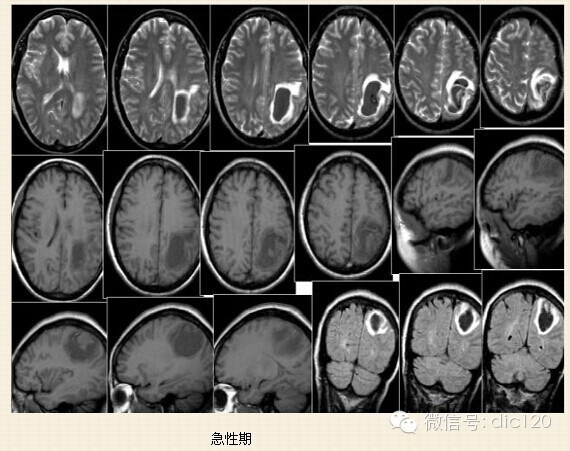

2.急性期(7-72小时):红细胞脱水萎缩,主要含有脱氧血红蛋白,此期灶周水肿,占位效应明显。

3.亚急性期(3天-2周):红细胞内主要为正铁血红蛋白,水肿及占位效应减轻。

4.慢性期(2周后):水肿消失,正铁血红蛋白演变成含铁血黄素,血肿小可填充,大则遗留囊腔。